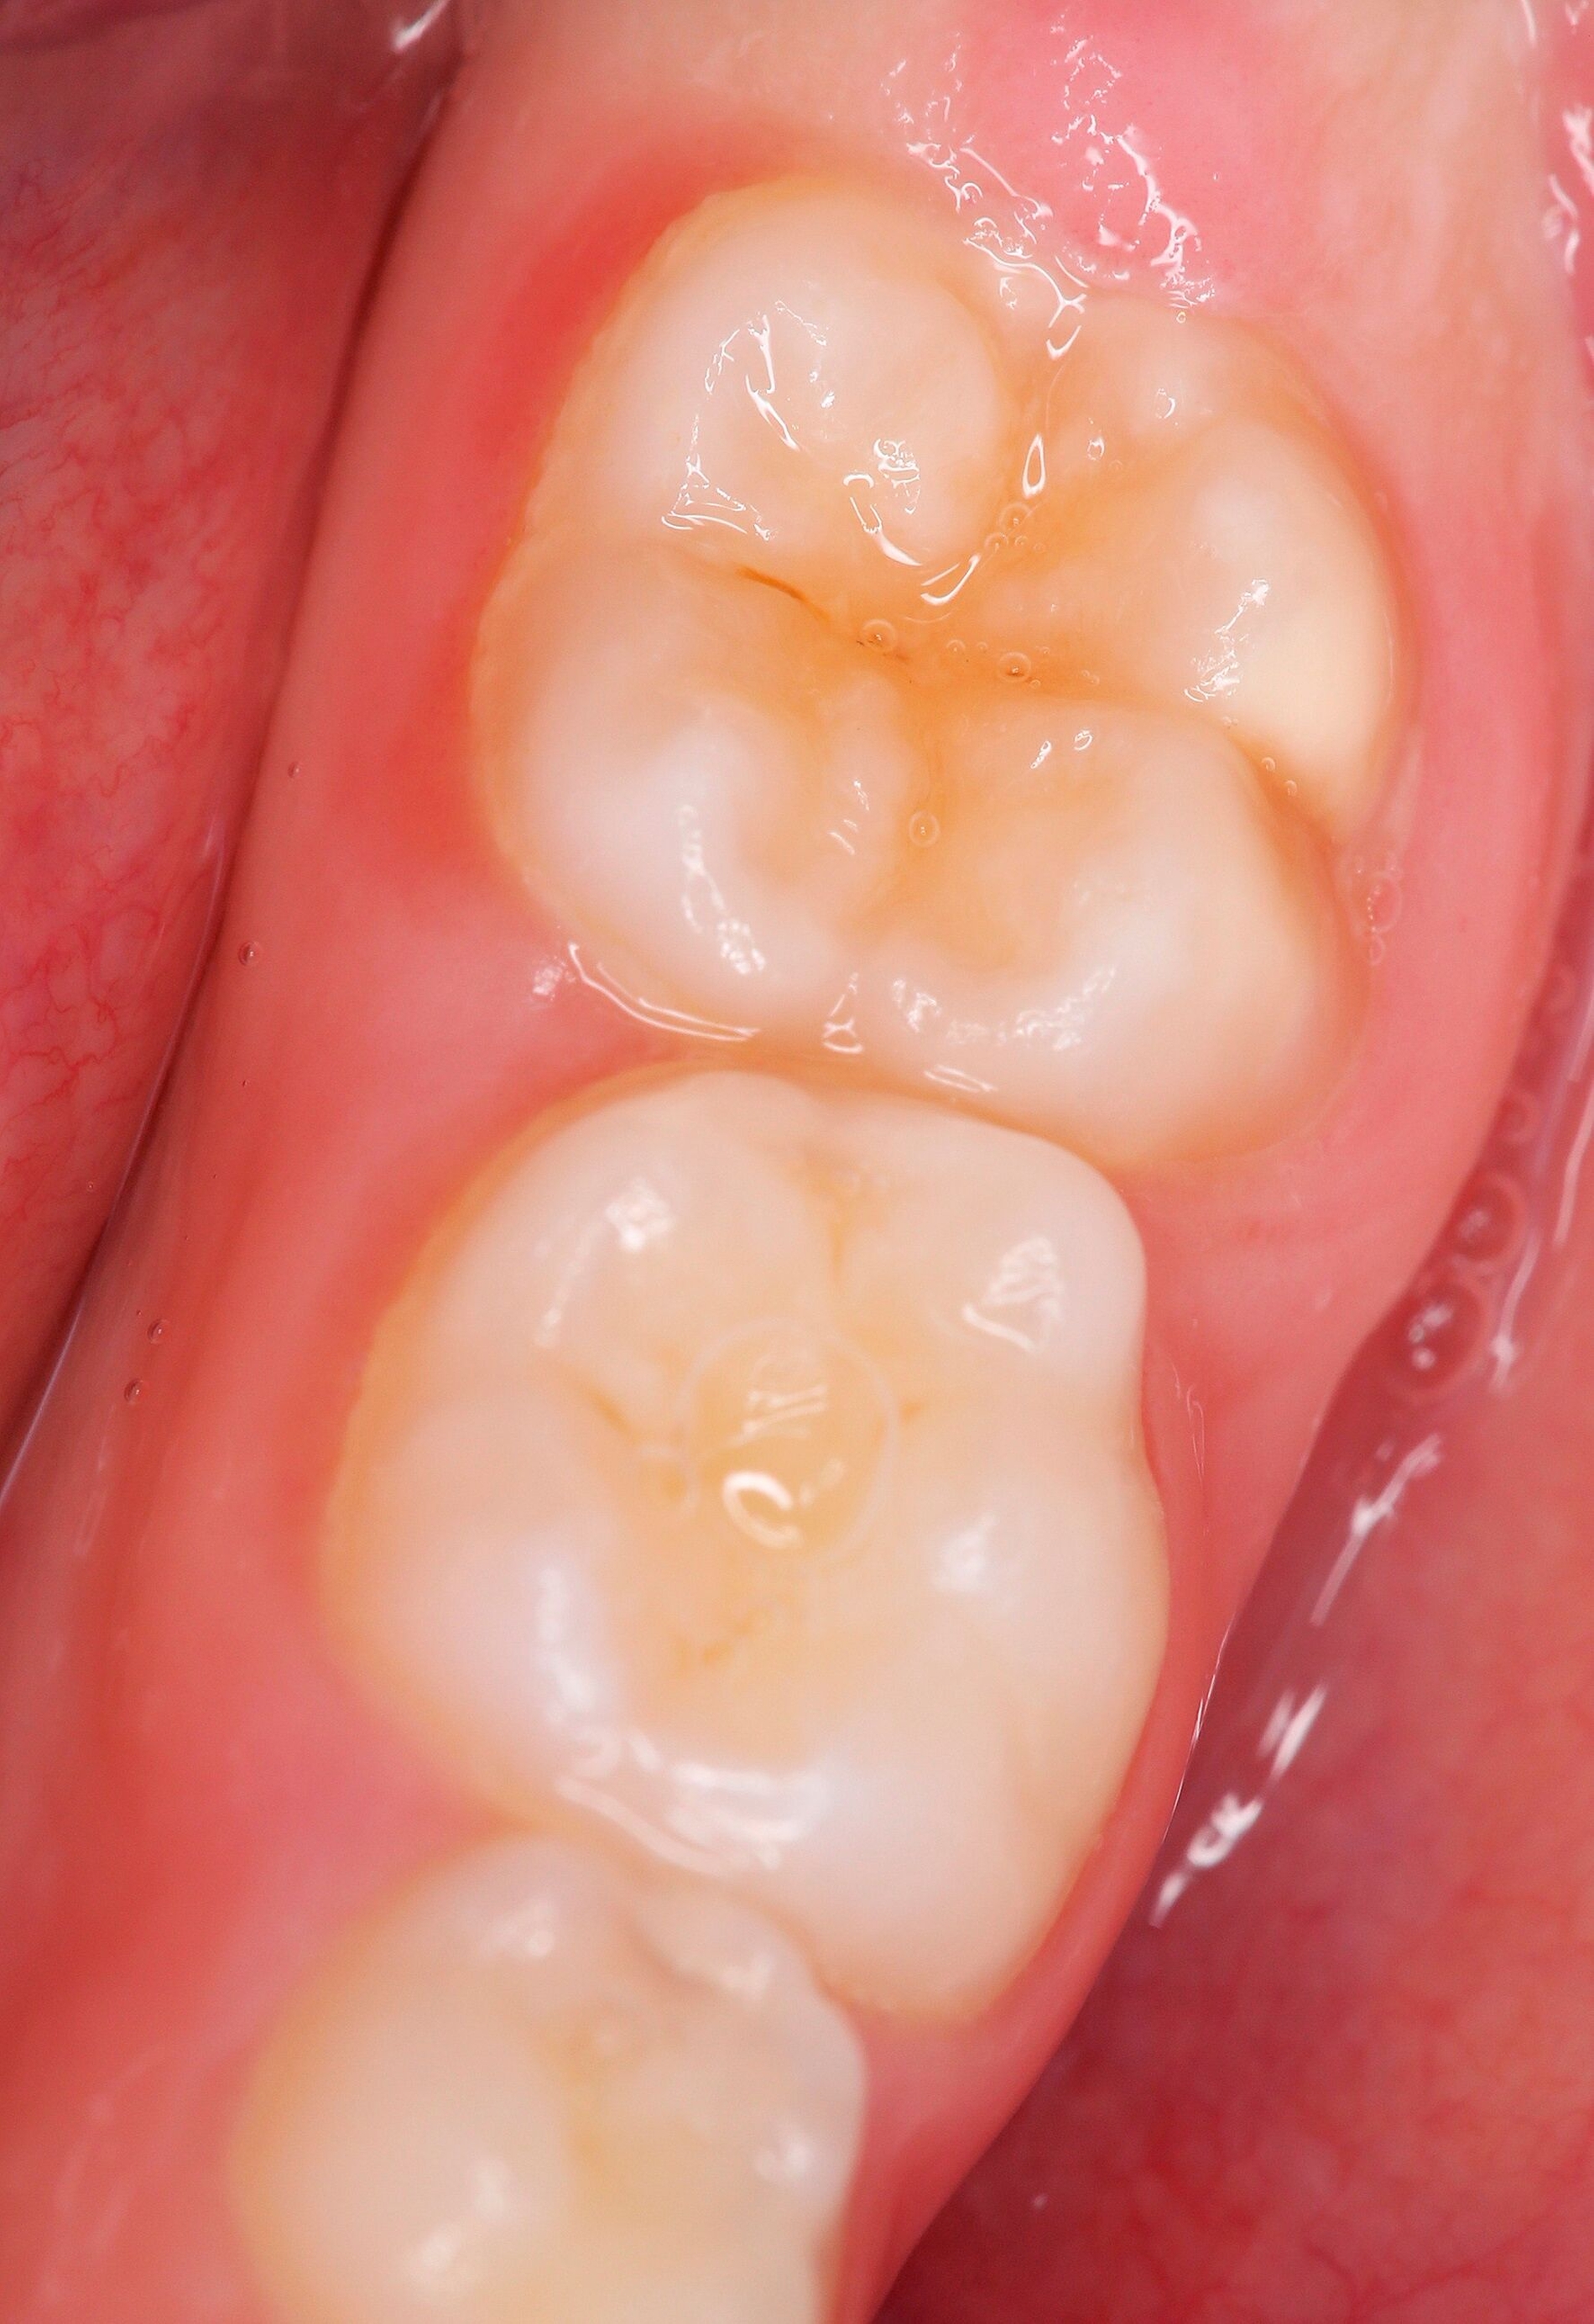

Die Ausprägung der Mindermineralisation kann stark variieren (Abbildungen 3 und 4). Klinisch zeigen sich an den betroffenen Zähnen unterschiedlich starke Verfärbungen beziehungsweise Opazitäten bis hin zu ausgeprägten Schmelzverlusten. So kann die Mineralisationsstörung im Bereich der Molaren auf einzelne Bereiche beschränkt sein, das Fissurenrelief einbeziehen oder sich über die gesamte Glattfläche erstrecken [Koch et al., 1987]. Bei den Inzisiven ist die Mindermineralisation bukkal zu finden. Geringgradig betroffene Zähne sind dabei eher durch weiß-gelbliche oder gelb-braune, unregelmäßige Verfärbungen gekennzeichnet, schwere Hypomineralisationsformen weisen dagegen abgesplitterte oder fehlende Schmelz- und/oder Dentinareale unterschiedlichen Ausmaßes auf.

Sind bei einem Patienten mehrere Molaren betroffen, so kann es auch hier zu Variationen kommen. Dementsprechend kann es sein, dass bei einem Molaren kleine, intakte Opazitäten zu finden sind, während an einem anderen Molaren große Teile des Schmelzes bereits kurz nach dessen Eruption einbrechen [Weerheijm, 2004].